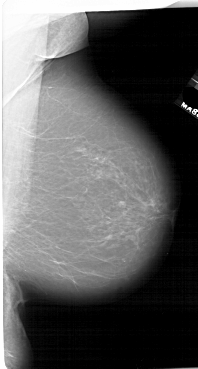

A_1649_1.RIGHT_MLO

RIGHT_MLO LINES 6631 PIXELS_PER_LINE 3556 BITS_PER_PIXEL 12 RESOLUTION 43.5 NON_OVERLAY